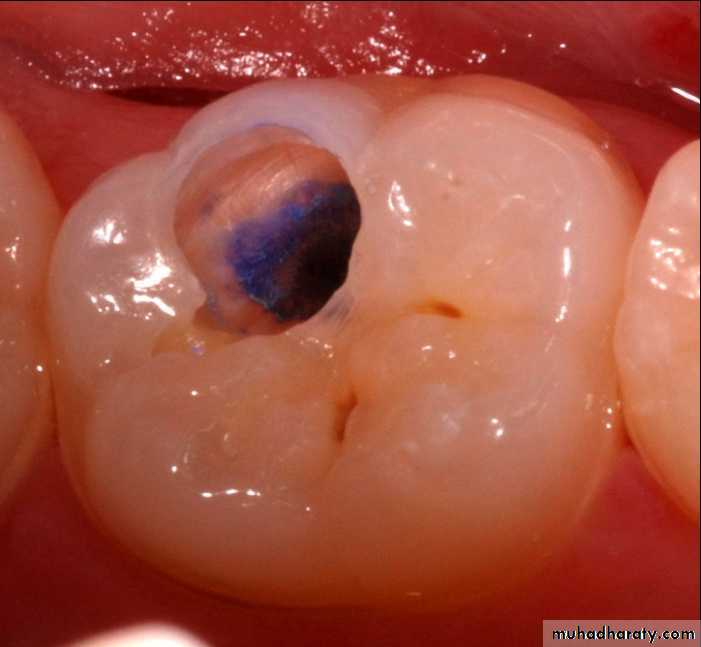

Dye penetration method

Use of basic fuschin in propylene glycol for the diagnosis and treatment of carious dentin has been given by Fusayama, 1980. The dye was found to be carcinogenic.To overcome this disadvantage, acid red or methylene blue were used, but methylene blue is slightly toxic.